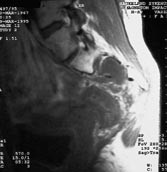

Ved nydebuterende isjias hos eldre pasienter bør tilgrunnliggende kreftsykdom alltid utelukkes. Langvarig, progredierende isjias hos yngre pasienter kan også i sjeldne tilfeller skyldes svulster i bekkenet, spesielt sarkomer, og muligheten for kreftsykdom bør overveies ved atypiske eller behandlingsresistente symptomer eller ved dårlig samsvar mellom kliniske funn og røntgenfunn (fig 1).